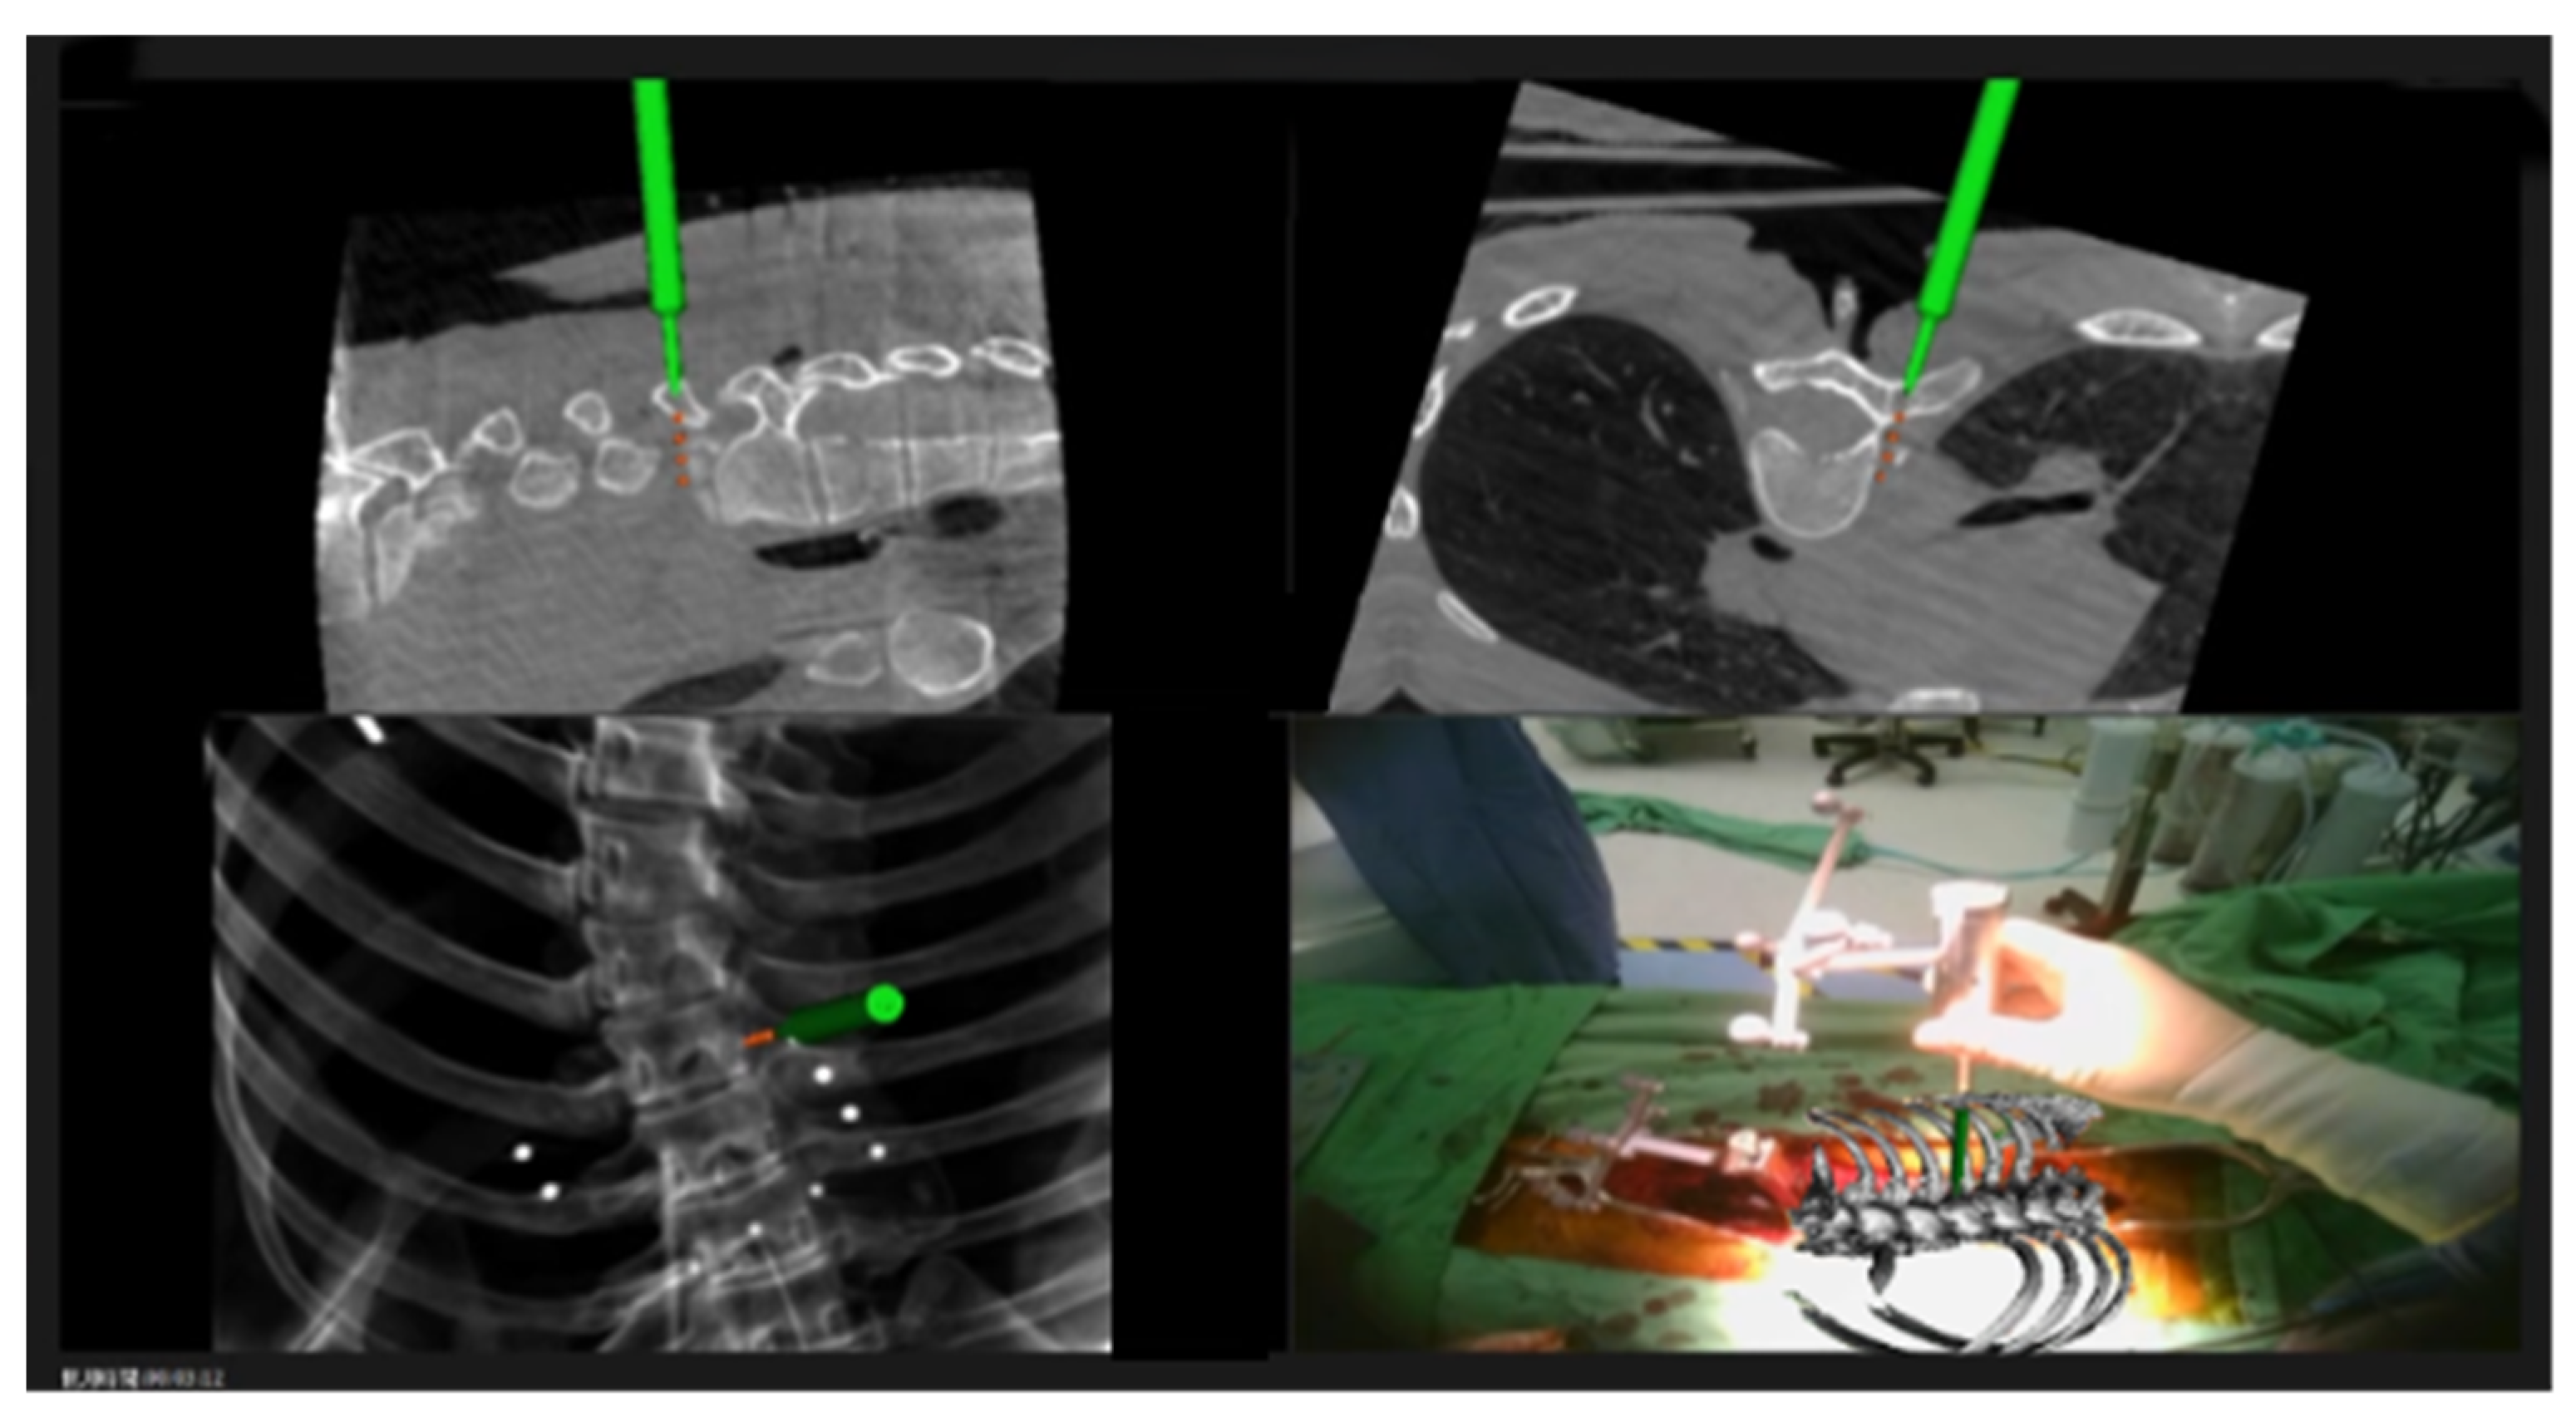

2.2. Registration Procedures

2.3. Surgical Techniques